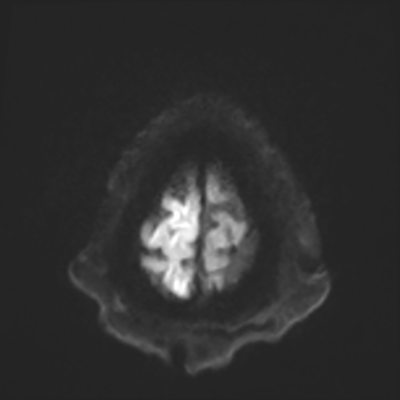

You come back the next day and see how things are going. The patient's electrographic record has shown a moderate encephalopathy (diffuse slowing, disorganization) with frequent right posterior quadrant delta slowing. Based on this result, and an adequately improved clinical examination, you give the okay to proceed with obtaining an MRI of his brain. This is shown below.

MRI brain (DWI)